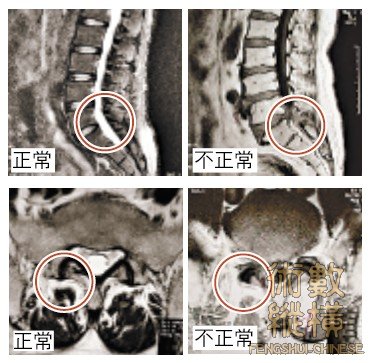

■對照左右照片,可以清楚地發現椎間盤受到擠壓的情形。

照片提供╱張志儒醫師